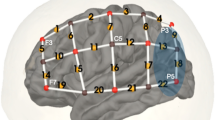

In addition to performing map-wise analyses across the optode arrays, region-of-interest (ROI) ERAs (single-subject level responses for each condition) were calculated for a priori and post hoc ROIs. The primary a priori “auditory” ROI targeted temporal brain regions and comprised symmetrical channels 29 and 33 in the left hemisphere (LH) and channels 7 and 12 in the right hemisphere (RH), the selection of which was based upon our previous fNIRS work involving auditory stimuli with children of similar age (Mushtaq et al. 2019). A pair of secondary a priori ROIs targeted “left inferior frontal” regions (channels 26, 31, and 35 in the LH) and “left posterior temporal” regions (channel 32 in the LH). Again, the selection of these ROIs was based on previous fNIRS research conducted in our laboratory with the same optode array and comparable auditory stimuli (Lawrence et al. 2018; Mushtaq et al. 2019). The data-driven post hoc ROIs were defined based on results of the channel-wise fNIRS analyses and were included to clarify the nature of the effects observed in these cortical regions. See Fig. 1 for an illustration of the position of the 44 channels and our a priori ROIs.

fNIRS measurement channel locations and a priori regions of interest. The channels outlined in blue form the superior temporal ROIs, which are located symmetrically in the LH and RH. The channels outlined in orange form the left inferior frontal ROI. The channel outlined in purple forms the left posterior temporal ROI